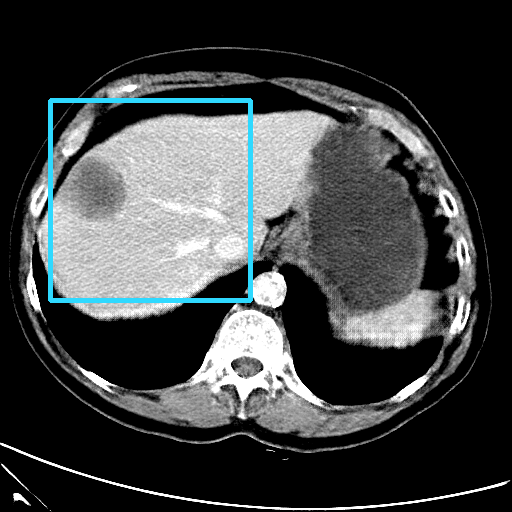

Refer to caption

(a) CT images.

(b) MRI images.

Figure 6: Lossy compression based attack on CT images (a) and MRI images (b) with a specific channel numbers (C8050\mathrm{C^{50}_{80}}) for the EP and IT Scenarios. StolenEPD1\mathrm{Stolen}^{\mathrm{D1}}_{\mathrm{EP}} denotes the decompressed images in the EP Scenario with a reduced D1 decoder.

Compression-Fidelity Compromise. Based on the previous results, we have selected the decoder D1D1 and the configuration of the latent and hyperlatent variables C8050\mathrm{C^{50}_{80}}, as the optimal architecture of the HiFiC encoder-decoder pair. In Fig. 6, we display more specifically the compression and reconstruction quality performances. In terms of reconstruction quality, we obtain a PSNR of approximately 40 for CT images and around 38 for MRI images while the MS_SSIM values are close to 1. This indicates an excellent perceptual quality of the reconstructed images that are hardly discernible from the original ones. In terms of compression efficiency, the Pratio\mathrm{P}_{\mathrm{ratio}} for CT images is approximately 0.015, indicating that the lossy image compression-based attack generated compressed images are 67 times smaller than those produced by the lossless zipped image compression-based attack. For MRI images, the Pratio\mathrm{P}_{\mathrm{ratio}} is around 0.12, 10 times higher than that of CT images, which can be attributed to the presence of a large uniform background in the skull-stripped original MR images.